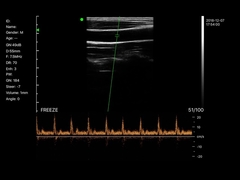

Kalite Portatif Ultrason tarayıcı, taşınabilir ultrason tarayıcı manufacturer from China